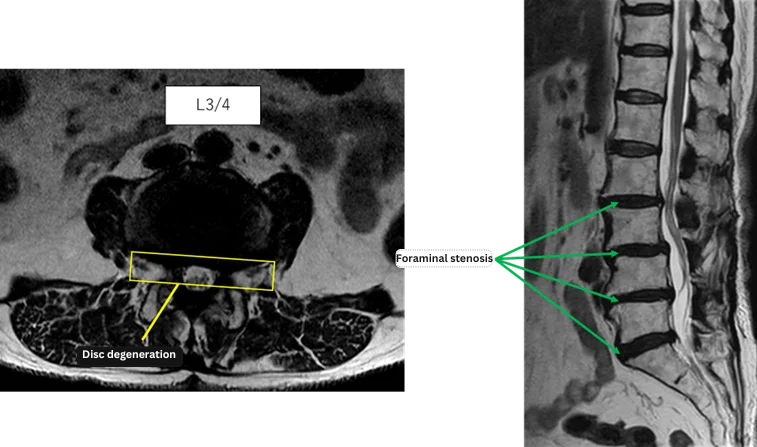

L1/2: No anomaly

L2/3: Disc degeneration

L3/4: Disc degeneration, bilateral foraminal stenosis

L4/5: Disc degeneration

L5/S: Disc degeneration

The above findings were also observed on the imaging.

Disc degeneration and foraminal stenosis at L2/3, L3/4, L4/5, and L5/S were considered highly likely to be the primary causes of her symptoms.